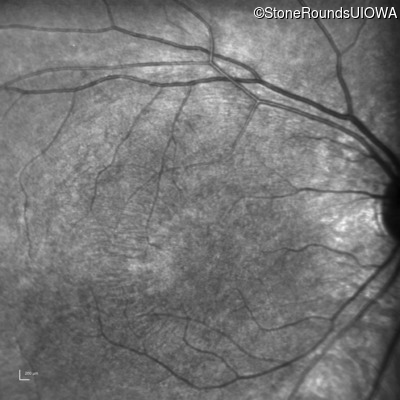

Infrared Fundus Photograph - Left - 5/200

Exemplar